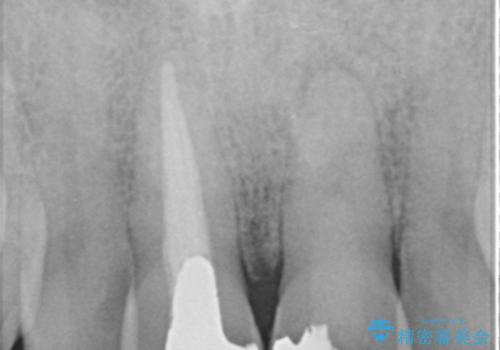

X線写真より、根尖部に透過像が認められ根管治療・ファイバーコア築盛・セラミッククラウンの作製が必要な状態です。

歯ぐきからの出血・排膿がある場合、根管内の感染や 歯肉炎・歯の破折などが考えられます。

X線検査や歯周組織検査などを行い適切な治療を行うことで良好な結果を得ることができます。